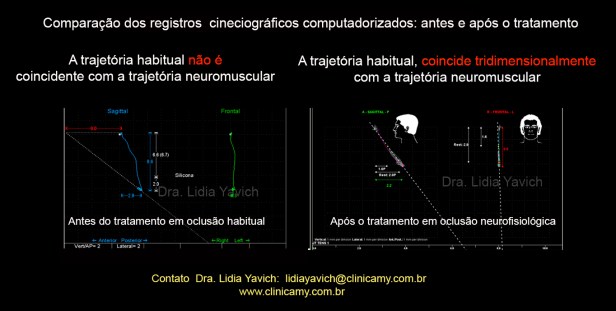

Comparação dos registros cineciográficos computadorizados: antes e após o tratamento.

Abertura bucal do paciente passou de 32,9 mm para 38,9 mm.

Excelente velocidade de abertura e fechamento.

Comparação de registros após desprogramação mandibular: antes do tratamento a trajetória habitual não é coincidente com a trajetória neuromuscular.

Após o tratamento a trajetória habitual coincide tridimensionalmente com a trajetória neuromuscular.